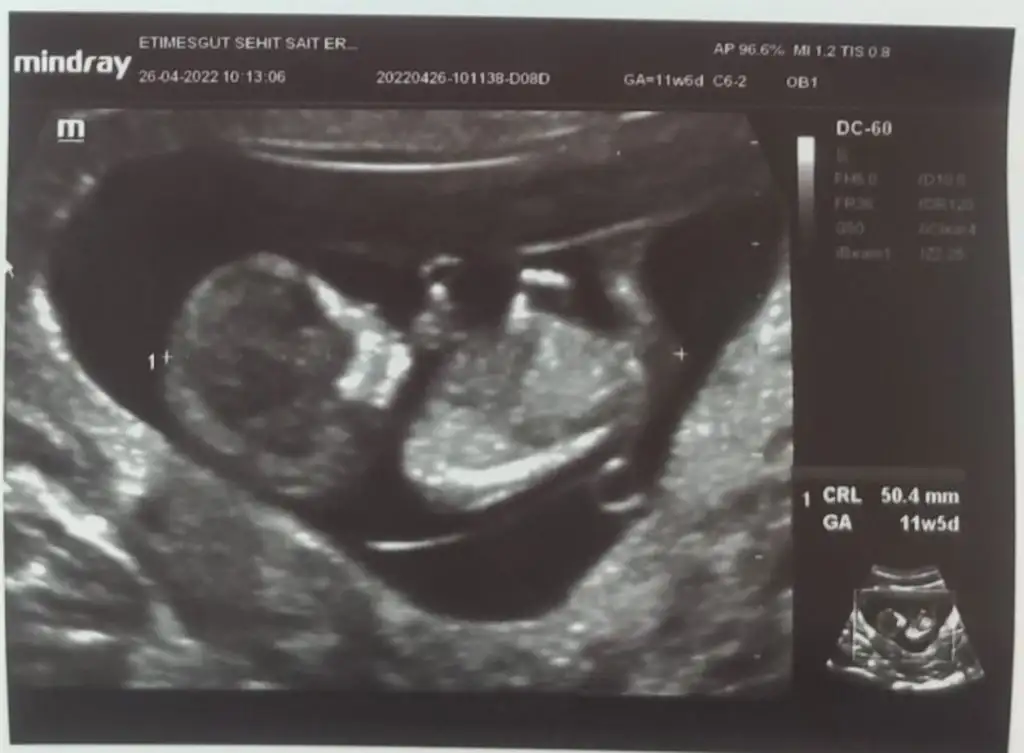

Çok teşekkür ederim doktor da erkeğe benziyor dedi ama kesin konuşmadı 3 hafta sonra netleşecek inşallah

inşallah 2 tane kızım var.bu da paşa olursa sevinirim.cevap için teşekkürler.belli olunca haber vericem :)paşa gibi